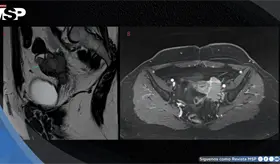

Las prótesis antiguas de metal con metal pueden liberar partículas microscópicas que generan inflamación severa, masas que imitan tumores malignos y, además, crean un ambiente propenso a infecciones profundas difíciles de tratar.